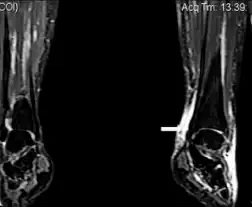

| Image with extensive epifascial edema in left foot of individual with secondary lymphedema | |